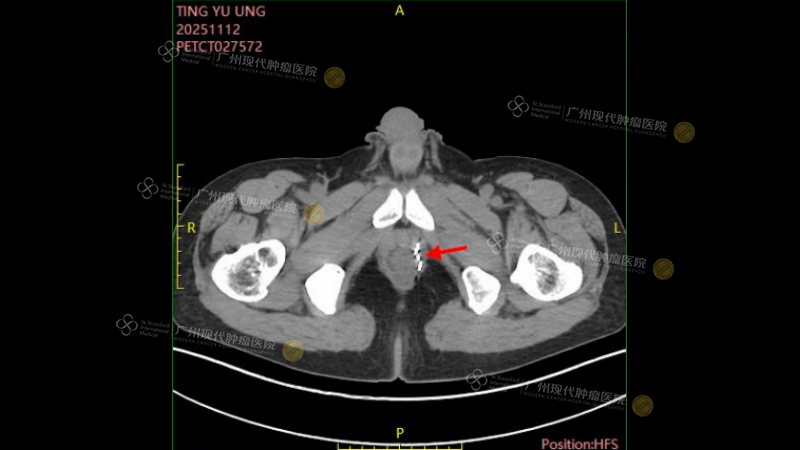

According to the latest CT imaging assessment results on November 12, 2025, the prostate tumor and lymph node lesions in Mr. Chen have basically been completely inactivated! This good news brought great comfort to Mr. Chen and his family, and their smiles became more frequent. We believe that this interim victory stems not only from the precise effectiveness of advanced technology but also from Mr. Chen's own resilience, optimism, and active cooperation. The road ahead is bright, and we are full of confidence as we look forward to the next piece of good news with him.

(On November 12, 2025, the latest CT results showed a significant reduction in tumor activity)